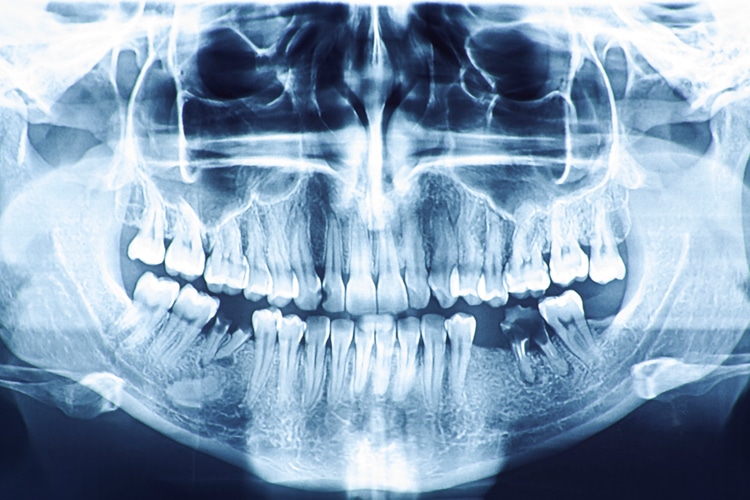

The oral cavity provides myriad ways of aiding the forensic identification process. Bone examination can be used for reconstruction purposes. In addition to the facial bones, cone-beam computed tomography, radiographs and photographs can be used to reconstruct an individual’s face. The presence of implants and joint replacements can also help identify an individual; similarly, salivary DNA analysis may also be used. The presence or absence of particular teeth and the position of various teeth can aid identification. Exact and correct documentation is paramount, as this information could be used for comparative purposes when needed to identify an individual.

The post-mortem dental examination is conducted by the authority and under the direction of the coroner/medical examiner or the designee, typically a forensic deontologist. Examinations are usually conducted in a morgue setting or temporary station set up at the scene of a mass disaster. Once the body is ready for evaluation, computer equipment can be used while information is collected for the comparison of postmortem and antemortem data. The tools used by the examiner to analyze and collect data include items typical of routine dental examinations, such as intraoral cameras, handheld radiography units, and computers with programs for item analysis. Remains are charted using a description that is similar to an intraoral examination.